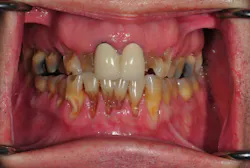

As with most projects, we must begin with the end goal in mind. In dentistry, that means developing a treatment plan prior to starting any treatment. In my practice, we use a process that allows us to simplify our treatment plans and produce predictable outcomes. The process we use is based on the systematic approach pioneered by Dr. Peter Dawson, founder of The Dawson Academy. Any dentist can properly diagnose even the most complex dental problems by following this method. In this article, I will outline our plan in a series of simple steps to develop a structured treatment plan that you can follow to reproduce similar plans with predictable results for your complex cases.

Before we start prepping teeth, we have to be certain that our foundation is sound, which means establishing biologic health, including addressing periodontal concerns and caries control.

Next, we are ready to transfer the information from the wax-up to the mouth using a series of putty stents and guides to fabricate the provisional restorations (more details are listed below). During this step, we work out the finer details of design using phonetics and arc of closure to refine edge position and lingual contour.

Once the patient is completely comfortable and happy with the provisionals, we take a new set of photos, facebow, bite registration, and models to communicate with the ceramist, who will complete the fourth version of the case—in porcelain.